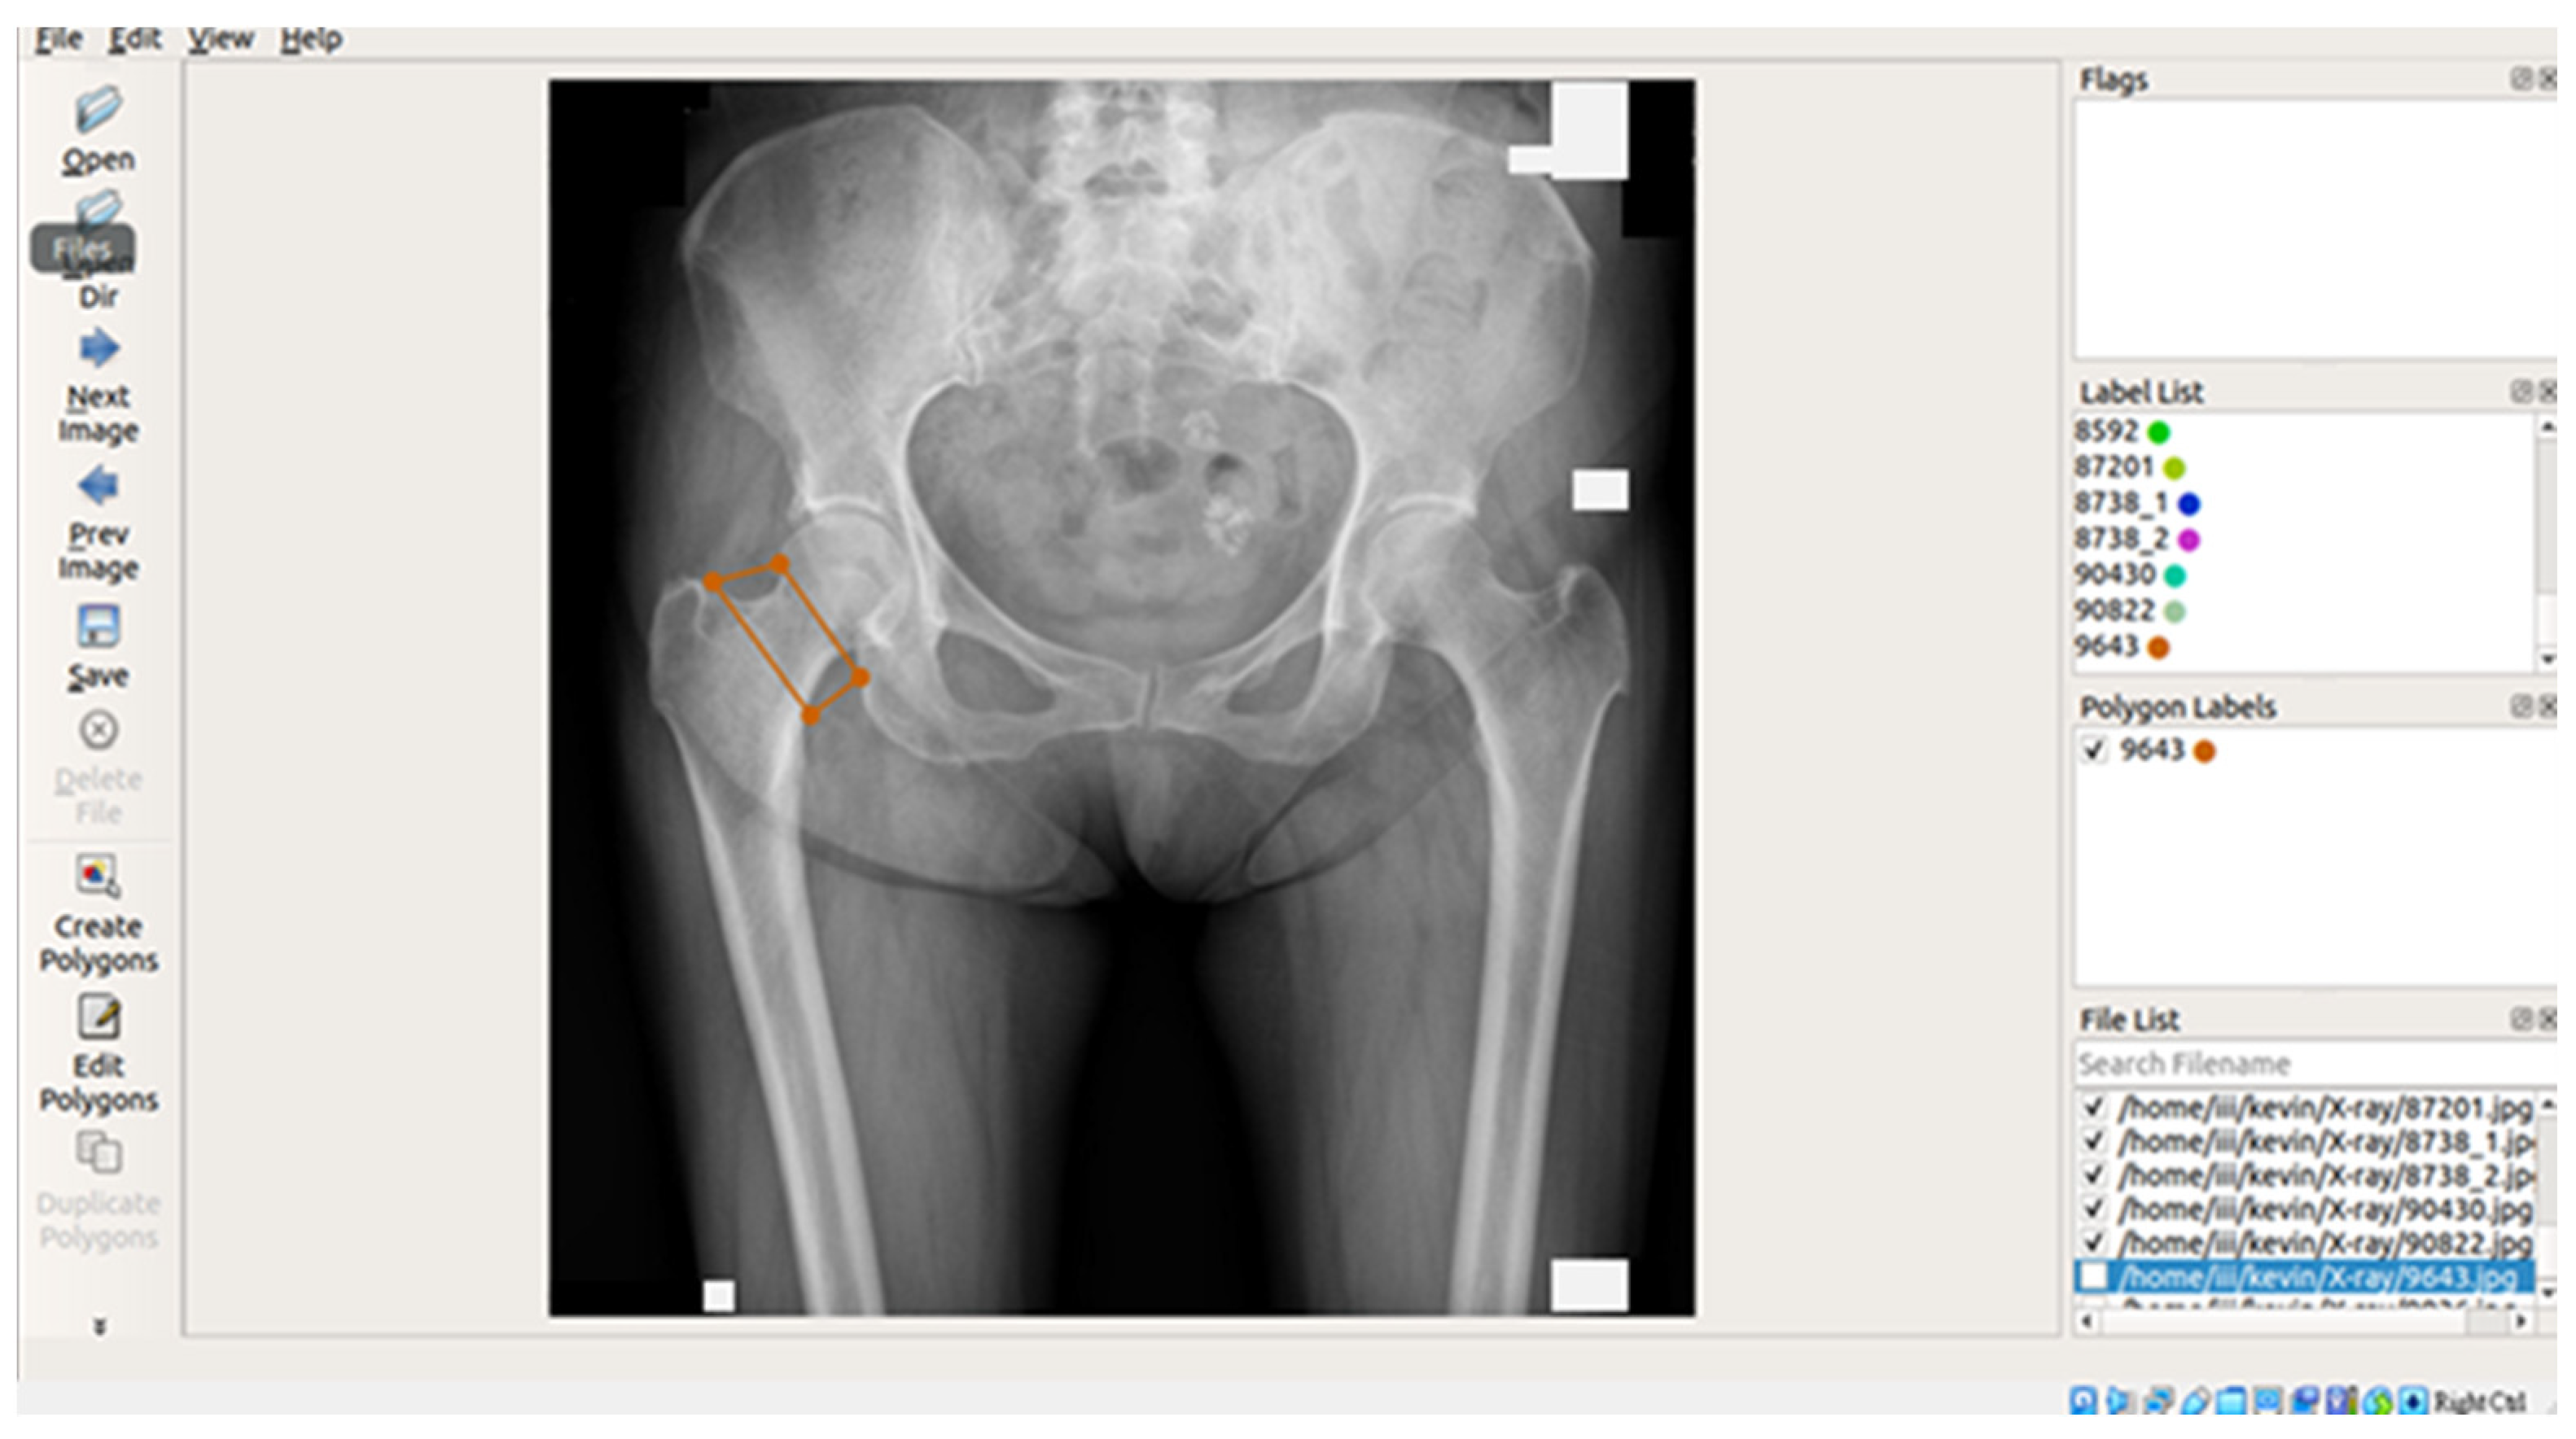

In this study, X-ray images of each of the four areas of the patient’s hip (femoral neck, greater trochanter, Ward’s triangle, and total hip) were separated and manually labeled using Labelme, an open-source tool that can be used for labeling [29]. The four parts of the hip were then framed as shown in Figure 2 below, and the labeled image data were batch converted into binary png files, which were used as inputs for the supervised learning training of U-Net, U-Net++, and image categorization in the image segmentation process.

3.3.2. Image Segmentation